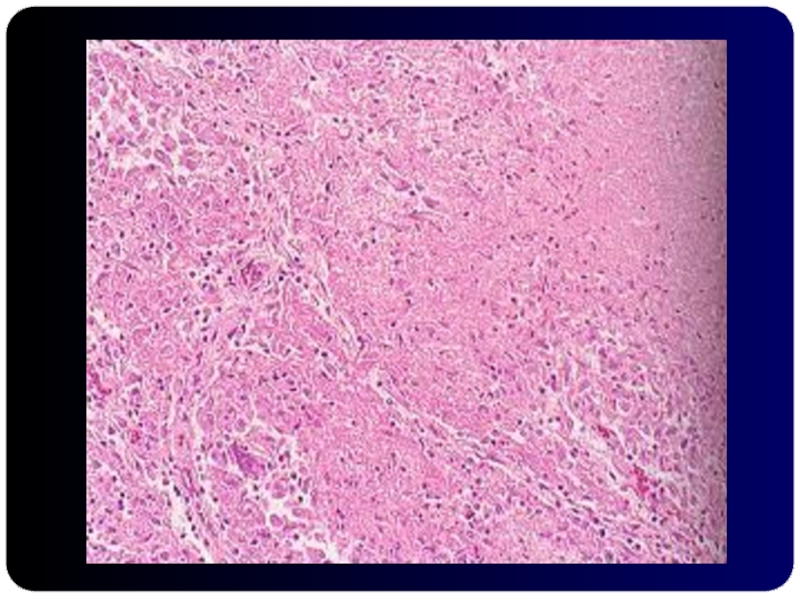

Слайд 26Микобактериоз при СПИДе Веретеновидные гистиоциты в лимфатическом узле

Микобактериоз при СПИДе Веретеновидные гистиоциты в лимфатическом узле